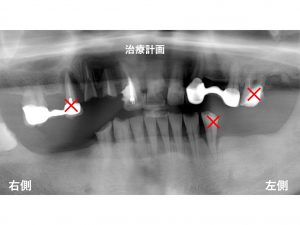

以下が初診時です。

下顎の左右の奥歯が欠損しています。

それ以外にも多くの問題がありました。

上顎右側の奥歯は、

根の先まで骨吸収があり、グラグラです。

患者様も痛くて 噛めないとおっしゃっています。

その隣の歯は、取れてしまったままでいました。

歯がないままですので

噛めないだけでなく、

審美的にも問題があります。

早急に仮歯を作成することが必要です。

それ以外にも

虫歯が非常に大きかったり

上顎左側の奥歯では、

歯周病によって根の先まで骨吸収が進んでいました。

下顎の左側の奥歯も

グラグラです。

治療計画ですが、

まずしっかりと噛める状態を作らないといけませんので

早急に仮歯の作成を行います。

抜歯行いながら

仮歯を作成していきます。

以下の×印の歯は抜歯です。

抜歯と同時に

上顎の右側の奥歯に仮歯を作成します。

上顎の前歯から左側の部分にも仮歯を作成します。